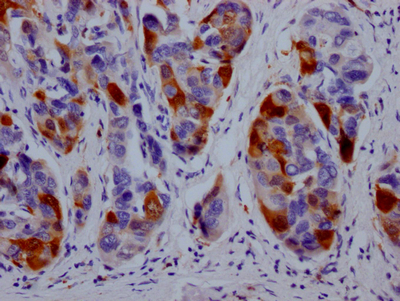

IHC image of CSB-RA264582A0HU diluted at 1:100 and staining in paraffin-embedded human breast cancer performed on a Leica BondTM system. After dewaxing and hydration, antigen retrieval was mediated by high pressure in a citrate buffer (pH 6.0). Section was blocked with 10% normal goat serum 30min at RT. Then primary antibody (1% BSA) was incubated at 4℃ overnight. The primary is detected by a Goat anti-rabbit IgG polymer labeled by HRP and visualized using 0.05% DAB.